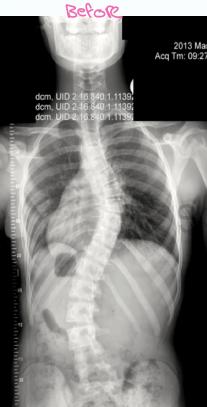

Surgical Treatment

Indications:

- Curves >40° in skeletally immature patients

- Progressive curves

Procedure:

- Correction

- Instrumentation

- Fusion

Surgery

- Adult documented progressive curves